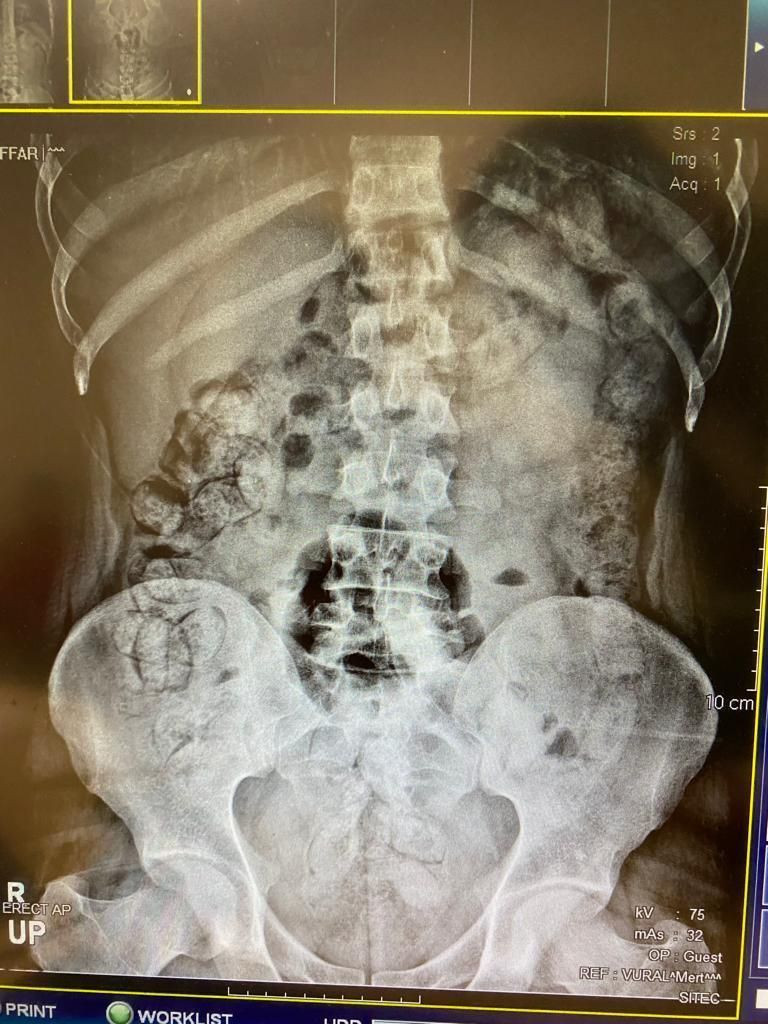

Bir otomobilde durumlarından şüphelenilen ve araçlarında yapılan aramada çantalarından "tokluk hissi veren" ve "bağırsak temizleyici" ilaçlar çıkan İran uyruklu Mehdı B, Mılad F. ve Sıraus G. gözaltına alınarak hastaneye götürüldü.  Çekilen röntgen filmlerinde şüphelilerin vücutlarında 62 kapsül eroin ve 210 kapsül afyon sakızı olduğu tespit edildi.

Röntgen çekimlerinde uyuşturucu kapsüllerinin şüphelilerin neredeyse iç organlarının her tarafına yayıldığı belirlendi. Doktor ve polis, vücutta tek seferde bu kadar yüklü miktarda uyuşturucu görmenin şaşkınlığını yaşadı.